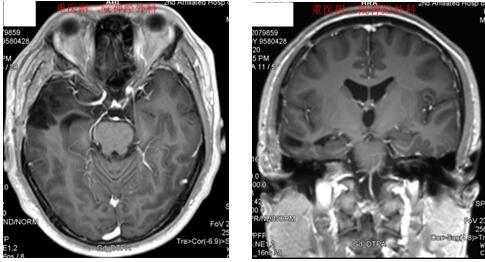

男性,32岁,因“反复癫痫发作5年”入院

术前MRI检查提示癫痫病灶位于右侧海马